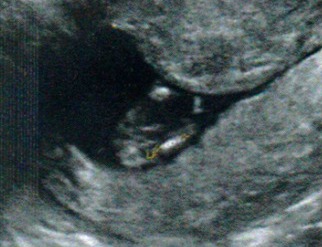

Here is another although this looks a little like 3 lines!

Attachment 21097